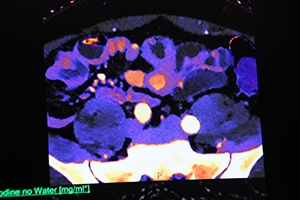

同一症例の仮想単色X線画像(45keV)。通常画像よりも明瞭に,複数の造影効果が認められる。 |

同一症例の実効原子番号画像。実効原子番号ごとにカラーリングされるため,よりいっそう腫瘍を鑑別しやすい。 |